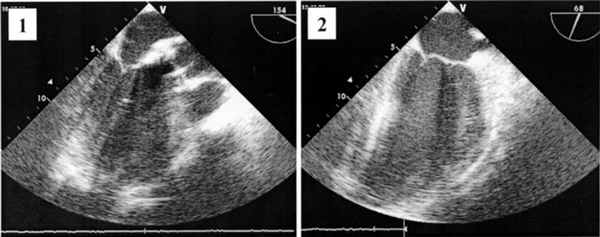

В послеоперационном периоде всем больным выполняли эхокардиографическое исследование. Отмечали достоверное снижение пикового и среднего градиентов давления на АК, что свидетельствует об эффективности хирургической коррекции порока. Пиковый транспротезный градиент после операции равнялся в среднем 17,9±9,2 мм рт.ст. (от 10 до 34 мм рт.ст.). Функция МК признана удовлетворительной у всех больных. Улучшилась подвижность передней створки МК (рис. 2). Рисунок 2. Эхокардиограммы. 1 - до операции; 2 - после операции. Регургитация на МК не превышала I-II степени. У 14 (12,9%) пациентов отмечалась регургитация II степени, у 51 (47,2%) - I степени. Длительность искусственного кровообращения составила в среднем 105,4±27,7 мин (от 54 до 225 мин), продолжительность пережатия аорты - 81,4±24,5 мин (от 39 до 183 мин). Динамика эхокардиографических показателей представлена в таблице.